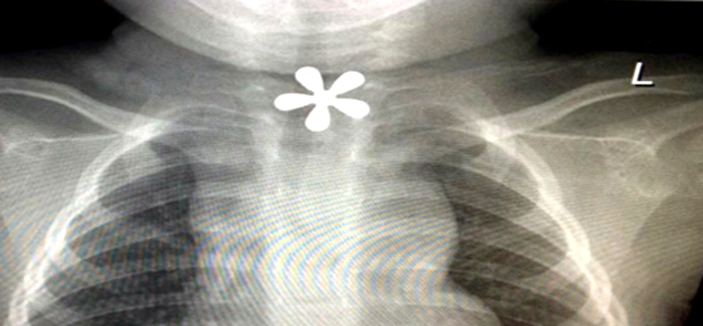

في حالة استنفرت أطباء مستشفى الملك فهد المركزي بجازان حين وصل طفل ابتلع جسما معدنيا في غفلة من الأسرة، وصل للمستشفى محولاً من مستشفى صامطة، ويعاني صعوبة في التنفس وأجريت له عملية في الحال..

وأوضح رئيس قسم الأنف والأذن والحنجرة بمستشفى الملك فهد الدكتور عبدالله يعقوب، أن طوارئ المستشفى استقبلت حالة لطفل يبلغ من العمر العام ونصف العام، وقد أجريت الإسعافات الطبية اللازمة وعقب ذلك أدخل الطفل لغرفة العمليات وأجريت له عملية استخراج بالمنظار وعاد الطفل لحالته الطبيعية واستطاع التنفس والبلع بشكل سليم وطبيعي.